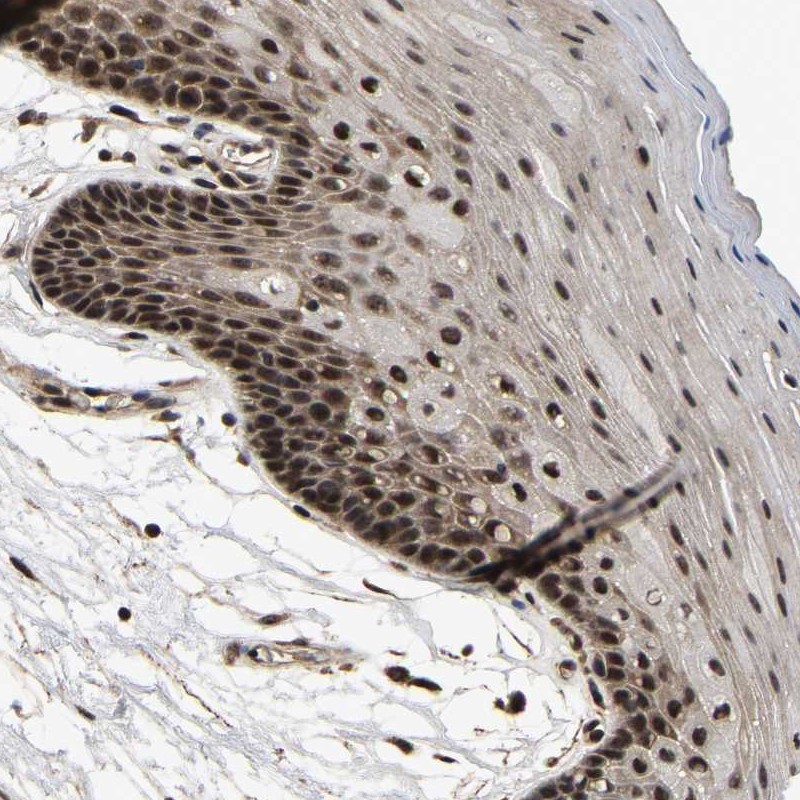

Immunohistochemical staining of human oral mucosa shows nuclear positivity in squamous epithelial cells.